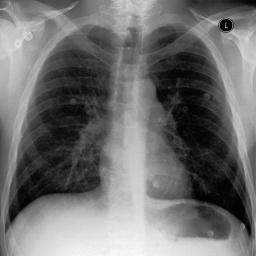

Fig. 3: Anonymization results. Real images XRX_{R} randomly selected from the training, validation, and test sets are displayed in the first column. The corresponding reconstructed images X^R\hat{X}_{R} are displayed in the second column. The anonymized images XAX_{A} are displayed in the last three columns.

Qualitative Results The visualization results are shown in Fig. 3. In this figure, the anonymized images optimized using only the utility loss ut\mathcal{L}_{ut} (column 3) exhibit greater visual similarity to their real counterparts (column 1), while those optimized using only the identity loss id\mathcal{L}_{id} (column 4) appear more distinct from their originals. Additionally, the anonymized images optimized with both the ut\mathcal{L}_{ut} and the id\mathcal{L}_{id} (column 5) strike a balance, appearing more realistic by simultaneously considering both identity removal and utility preservation.